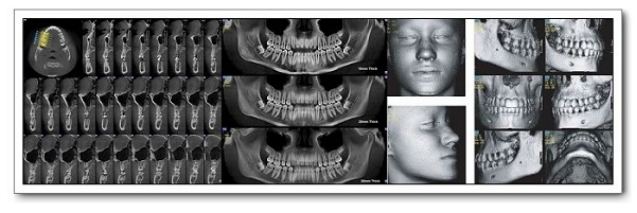

口腔影像科简介

2021-09-18

新疆医科大学附属口腔医院影像科是拥有多台先进数字化医学影像设备和较高专业技术水平的口腔影像专业化科室。新疆医科大学口腔医院影像科现有医护人员7名。具有硕士以上学历人员占比50%科室现有原装进口的德国口腔signora锥形束CT机一台,卡瓦Aero-X三合一一台,芬兰instrumentarium数字化曲面体层摄影机1台,卡瓦RVG一台,美国柯达数字rvg一台。主要开展医疗项目有对口腔颌面部囊肿、肿瘤、外伤、炎症、颞下颌关节、涎腺、牙体...查看详情 >